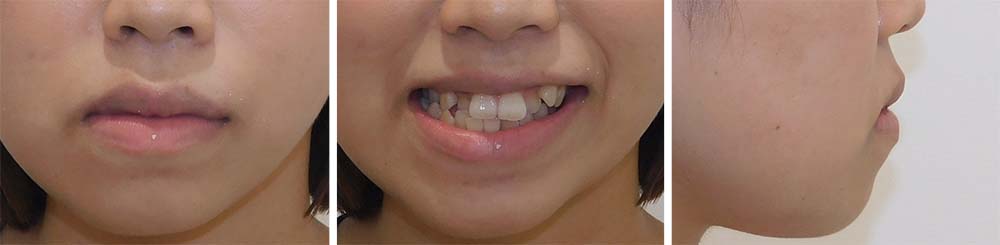

| 症例分類 | 顎変形症、叢生、下顎前突 |

| 診断名 | 下顎の左側偏位を伴う骨格性下顎前突 |

| 主訴 | 上下ガタガタ、受け口 |

|---|---|

| 年齢 | 15歳10ヶ月 |

| 性別 | 女性 |

骨格的に下顎が前方と左側に偏移しており矯正単独では治療が難しいため、上顎第一小臼歯を抜去して上下顎の手術を併用して治療することになりました。

1年7ヶ月の術前矯正後、上下顎の手術を行いました。

術後の顎間ゴムをしっかりと使用していただけたため、術後8ヶ月で治療が終了することができました。

下顎の前突感を改善することができました。